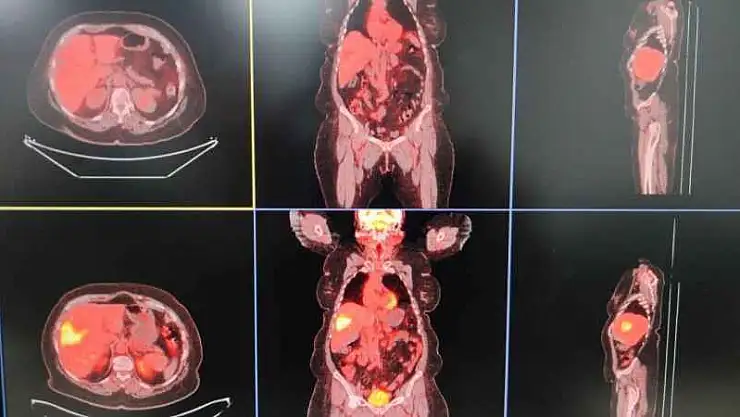

Diyarbakır Gazi Yaşargil Eğitim ve Araştırma Hastanesinde Radyoloji Uzmanı Ayhan Şenol, birimlerinde girişimsel radyoloji olarak hastalıkların tanısı, tedavisi ve takiplerini yaptıklarını söyledi. Hastaların biyopsi, sonografik ve tomografik yöntemlerle tanılarını koyduklarını dile getiren Şenol, “Genel olarak hastalığın bulunması için tüm işlemler yapılabilmekte. Hastalıkların biyopsi veya sonografik-tomografik yöntemlerle hastalıkların tanısını koyuyoruz. Bir kısmının da tedavisini yapıyoruz. TARE işlemi; belli organlardaki tümör hücrelerine hedef kitleyi besleyen damarın içine girip buna lokal olarak radyoembolizan dediğimiz maddenin enjekte edilmesiyle gerçekleşen bir işlemdir. Bu işleme yaygın olarak karaciğerin kendi tümörleri ile başka organlardaki tümörün yayılımlarını tedavi ediyoruz” dedi.

Nükleer tıp birimi ile işbirliği içerisinde hastalara tedavi uyguladıklarını ifade eden Şenol, “Bu servisimizde diğer birimlerle işbirliği yaparak çalışıyoruz. Nükleer tıp en fazla işbirliği yaptığımız birimdir. Hastaların çoğu buraya gelmeden nükleer tıp birimine görünüp öyle bize gelir. Hastanın uygunluğu araştırıldıktan sonra öncesinde burada tedavinin bir provası yapılır. Kitlenin besleyici damarı bulunup buraya bir prova olarak asıl vereceğimiz ilaca benzer bir ilaçla enjeksiyon yapılıyor. Daha sora nükleer tıp biriminde ilacın o kitleyi ne kadar tuttuğu hesaplanıp uygun dozlarda asıl ilaç dozu hesaplanır. Bir sonraki seansta aynı şekilde daha önce belirlediğimiz damarın içine girip radyoembolizan dediğimiz küçük parçacıklara radyoaktif maddeler yüklüyoruz. Biz bu parçacıkları küçük küçük doku içerisine gönderip hem belli bir süre tıkama hem de lokal olarak vücudun diğer taraflarına etki etmeden sadece kitleye etki edip onu öldürme yöntemini kullanarak tümörü tedavi ediyoruz” diye konuştu.